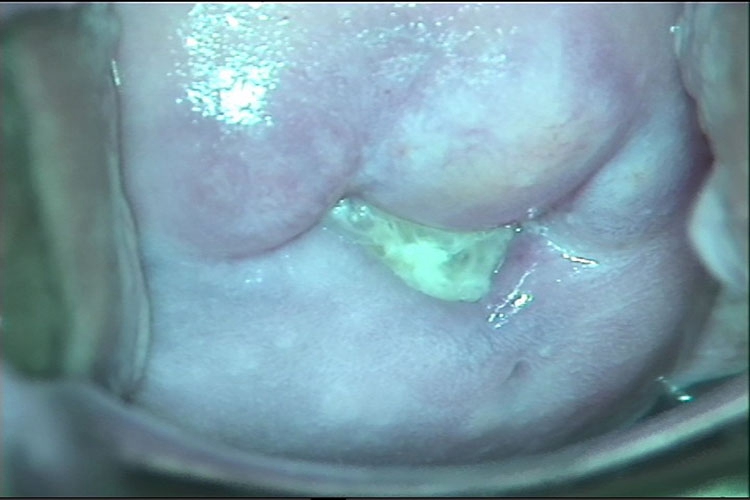

阴道:阴道裂伤及挫伤感染表现为黏膜充血、水肿、溃疡,以及脓性分泌物增多。